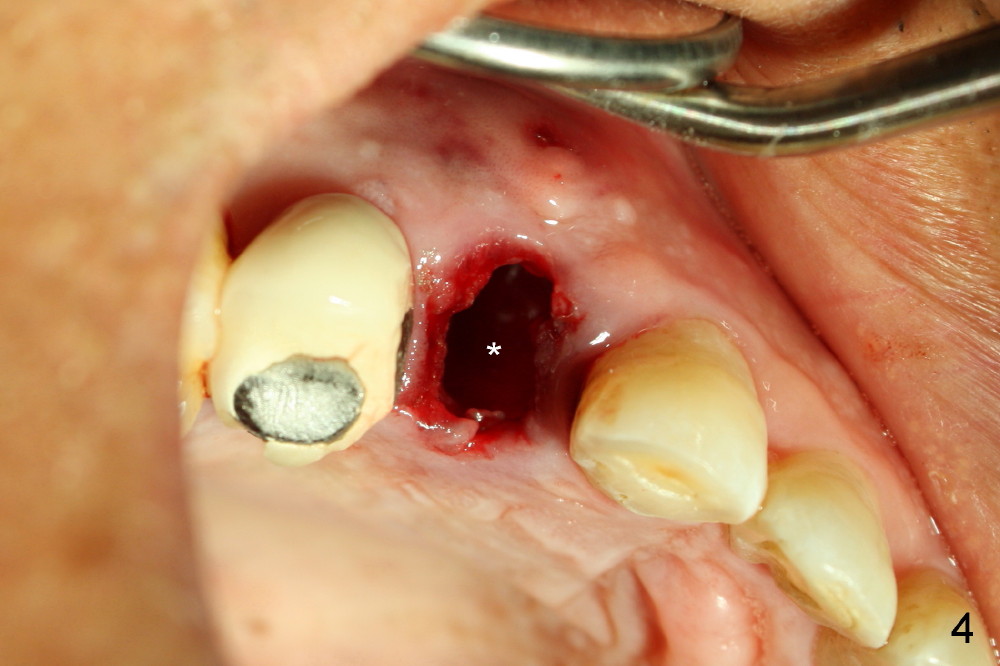

A 57-year-old man refuses treatment for the tooth #5 for 22 months (Fig.1). He suddenly shows up because of severe bleeding from the fistula of the tooth (Fig.2 <). After lengthened discussion, he agrees extraction (Fig.4) and immediate implant (Fig.5-8).